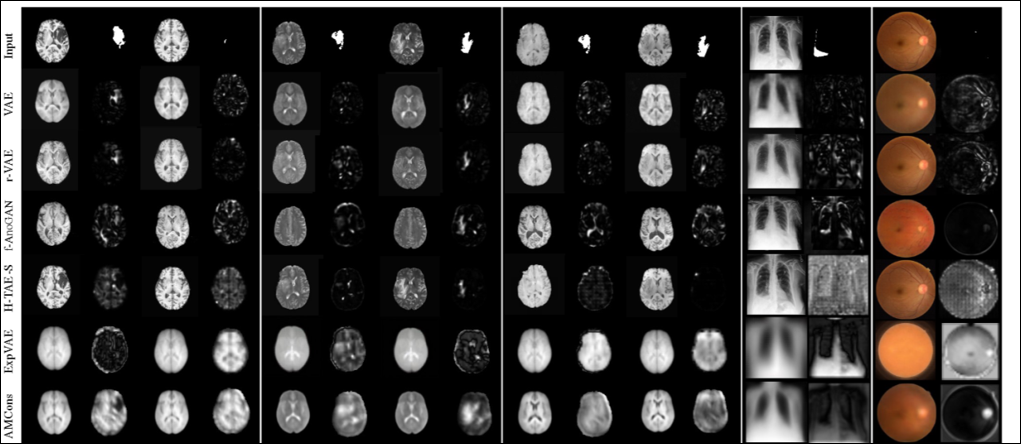

• I. Lagogiannis, F. Meissen, G. Kaissis and D. Rueckert

Unsupervised Pathology Detection: A Deep Dive Into the State of the Art

IEEE transactions on medical imaging, 43(1): 241-252 (2024)

DOI: https://doi.org/10.1109/tmi.2023.3298093